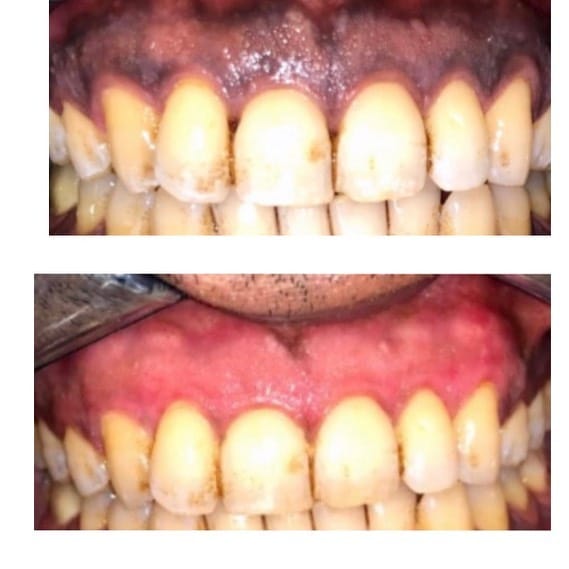

Siqaret və ya digər səbəblərdən yaranan rənglənmələrin götürülməsi

diş daşlarının təmizlənməsi